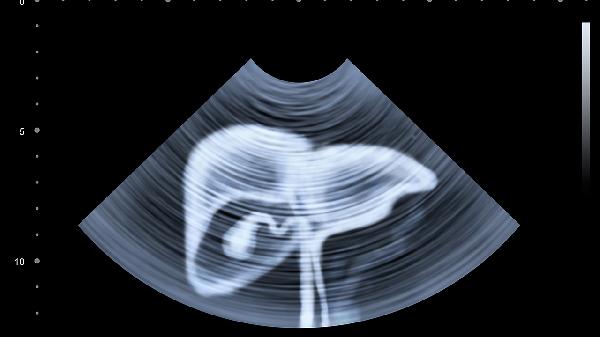

•监测两个信号:右肩隐痛+手掌红斑,出现任意一项建议立即拍肝脏B超